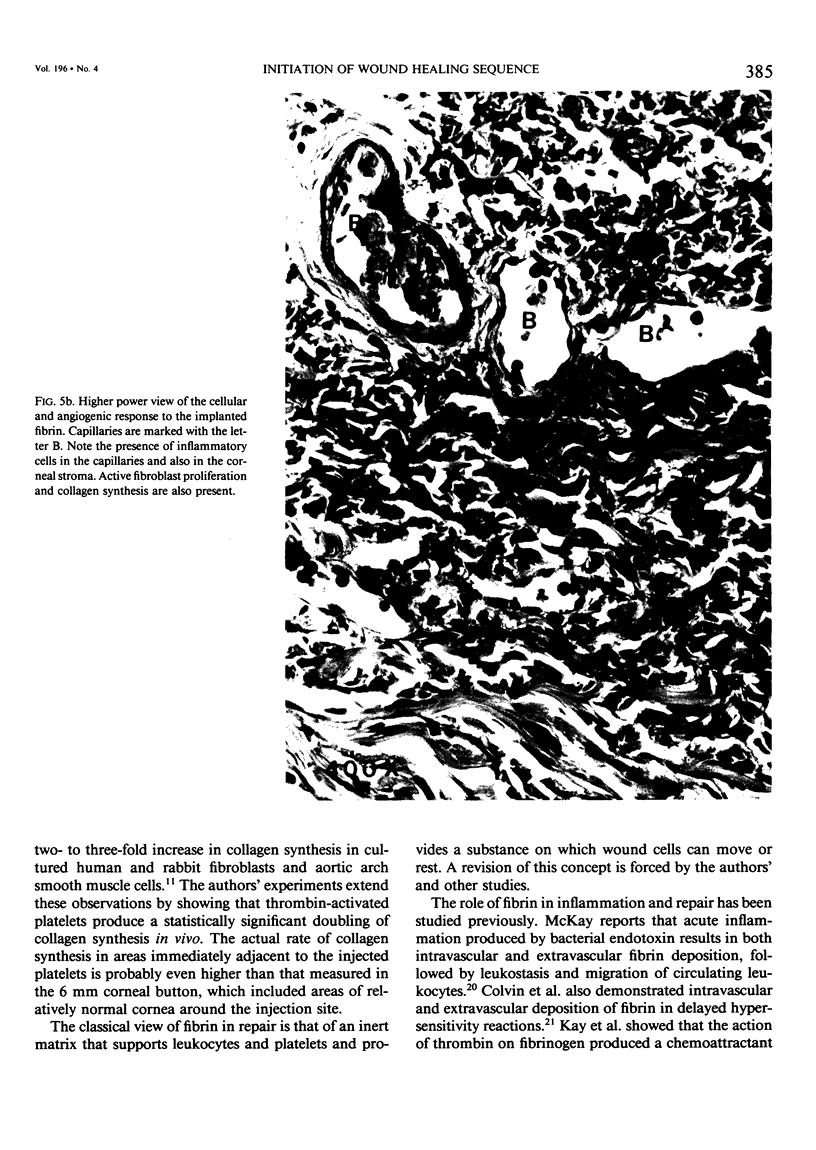

The signals that initiate repair are poorly characterized. These studies investigate the capacity of platelets and fibrin to initiate angiogenesis, fibroplasia, collagen synthesis and monocyte migration in the rabbit cornea assay. Methods: Autologous platelets and platelet-free fibrin were isolated from rabbit blood. Released and control platelet preparations and autologous and commercial fibrin were implanted in rabbit corneas. Results: Thrombin-released platelets produced angiogenesis and opacification. Histology showed fibroplasia, corneal thickening, and neovascularization. Collagen synthesis was elevated to twice control levels in thrombin-activated platelet preparations. Various control platelet preparations produced no angiogenesis, no opacification, and no histologic change. All fibrin injections elicited a cellular exudate from the limbal vessels, followed by angiogenesis and corneal opacification. Histology showed a mononuclear infiltrate with neovascularization and fibroplasia. Control injections of rabbit skin collagen and fibroblasts produced no response.